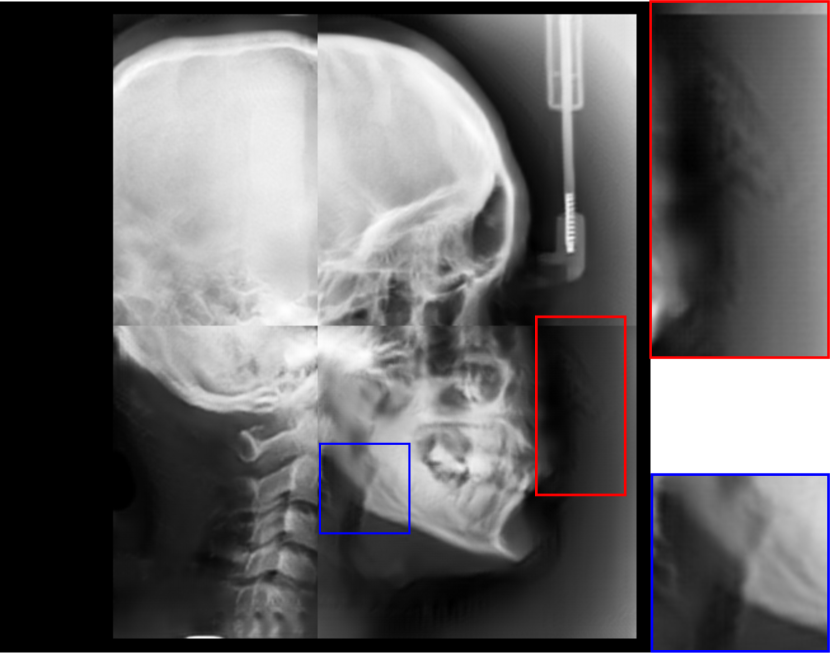

Fig. 8: Synthetic cephalogram examples from 3D CBCT volumes with different methods. (a)-(d) are comparison results while (e)-(h) are the (intermediate) results of our proposed method: (a) RayCast using orthogonal projection; (b) RayCast using perspective projection; (c) MIP using the largest 100 pixels along each orthogonal ray; (d) CycleGAN using patches from (a) and ISBI real conventional cephalograms; (e) RayCast using orthogonal projection from the skeleton enhanced volume; (f) original sigmoid transform of (e) using Eqn. (4) with air background recovery; (g) modified sigmoid transform of (e) using Eqn. (6), the final Type I synthetic cephalogram using orthogonal projection; (h) the final Type I synthetic cephalogram using perspective projection. The nose ROIs are redisplayed in the intensity window [0, 125] for better visualization. The mandible angle ROIs are for the visualization of the difference between orthogonal projection and perspective projection. The perceptual index of each synthetic cephalogram is displayed in the corresponding subcaption.

The synthetic cephalograms generated by different methods are displayed in Fig. 8. Figs. 8(a) and (b) show the cephalograms synthesized by the orthogonal [33] and perspective [21] RayCast methods, respectively, which are the most widely used methods for cephalogram synthesis from CBCT volumes. Comparing Fig. 8(b) to Fig. 8(a), due to different magnification factors of structures at different positions in perspective projection, anatomical structures on both sides of the midsaggital plane cannot overlap well, for example, the projections of the left and right mandible (gonial) angles in the zoom-in ROI in Fig. 8(b). In Figs. 8(a) and (b), the skeleton structures, soft tissues and airways are well observed. However, the image contrast in these two synthetic cephalograms are different from conventional cephalograms (Fig. 2(a)). The cephalogram synthesized by MIP using the largest 100 pixels along each orthogonal ray is displayed in Fig. 8(c). In this subfigure, skeleton structures are well observed since they have high intensity. Nevertheless, low intensity structures, e.g. the throat airway, might disappear. The CycleGAN [59] synthetic cephalogram is shown in Fig. 8(d). Compared with the conventional cephalogram example in Fig. 2(a), it has the closest image contrast. Hence, it achieves the best perceptual index of 5.53. However, some detailed anatomical structures are incorrect. For example, the nose has extremely low intensity in the zoom-in ROI. It also suffers from geometric distortion. As a consequence, the stitching artifacts are visible.

Figure 8(e)-(g) are the Type I synthetic cephalograms of different steps using orthogonal projection. Fig. 8(e) is the orthogonal RayCast celphalogram synthesized from the enhanced CBCT volume using Eqn. (1). Compared with Fig. 8(a), skeleton structures in Fig. 8(e) have higher contrast. Fig. 8(f) is obtained by applying the original sigmoid transform in Eqn. (4) to Fig. 8(e), where the skeleton structures are further enhanced. Moreover, the appearance of Fig. 8(f) is very close to conventional cephalograms. However, the soft tissues like the nose and lips have an almost constant intensity value, as displayed in the zoom-in ROI in Fig 8(f). The final Type I synthetic cephalogram with orthogonal projection is displayed in Fig. 8(g). With the proposed modified sigmoid transform in Eqn. (6), the contrast in the soft tissues is brought back, as displayed in the zoom-in ROI. For comparison, the final Type I synthetic cephalogram with perspective projection is displayed in Fig. 8(h). Compared with Fig. 8(g), the mandible angles in the zoom-in ROI of Fig. 8(h) are not overlapped well due to perspective magnification.